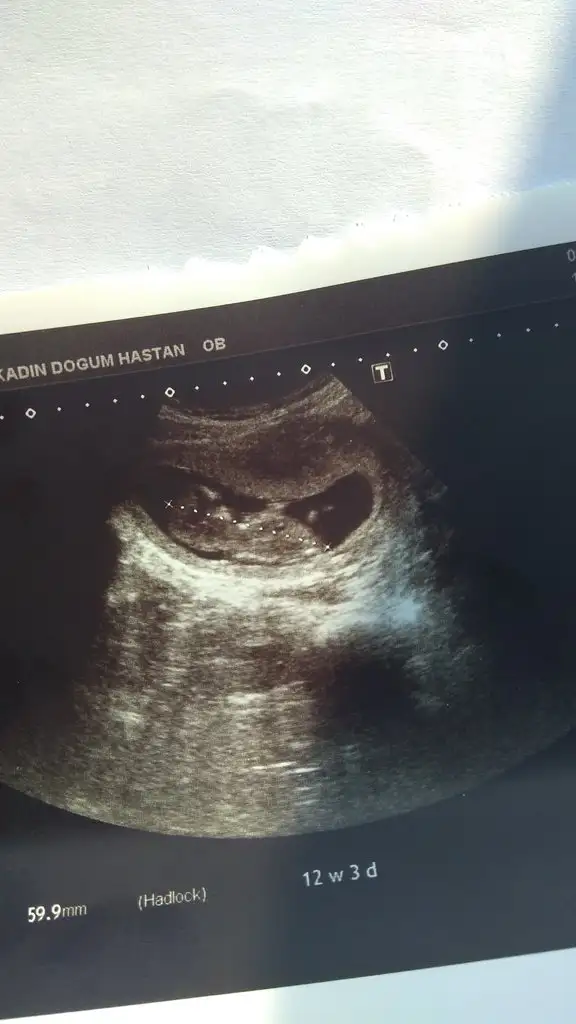

Sizce cinsiyet ne? 16+0 dayız

Eklentiler

• IMG-20190706-WA0008.webp

IMG-20190706-WA0008.webp

27,7 KB · Görüntüleme: 81